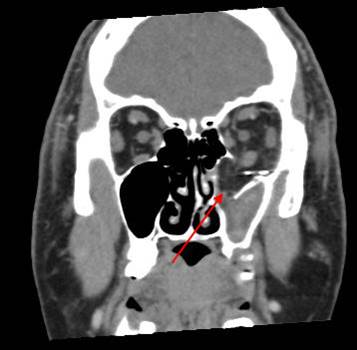

The mesial naso-orbito-ethmoid complex is fractured. Specifically, there is bony injury of the nasal bones or the frontal process of the maxilla and the medial walls of the orbit are abnormal. [Yes/No]

There is injury of the ethmoid complex. Specifically, the ethmoid roof, olfactory fossa and the cribriform plate are fractured and/or significantly dehiscent. [Yes/No]

There is bony injury of the body, alveolar ridge, premaxilla, the infraorbital rim, the palatine or the frontal process of the maxillary bones on either side. [Yes/No]